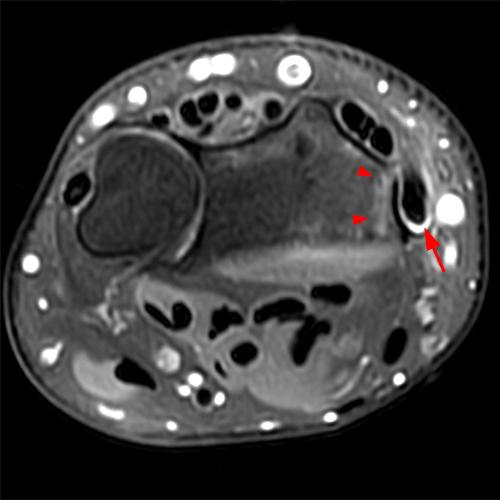

Clinical History: A 68-year-old female presents with radial-sided pain and swelling. Axial T1-weighted (1A), axial fat-suppressed proton density-weighted (1B), and coronal fat-suppressed proton density-weighted (1C) images are provided. What are the findings? What is your diagnosis?

Figure 2: The axial T1-weighted (2A), axial fat-suppressed proton density-weighted (2B), and coronal fat-suppressed proton density-weighted (2C) images demonstrate a thickened extensor retinaculum, surrounding soft tissue edema, and fluid signal in the first extensor compartment of the wrist (arrowheads). Marrow edema is noted within the subjacent radius (asterisks). A single extensor pollicis brevis and two abductor pollicis longus tendon slips are present with heterogeneous intrinsic signal.